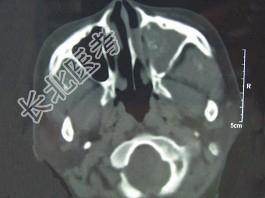

- 单项选择题男,41岁, 左侧鼻腔胀痛半年余,CT检查如图, 最可能诊断为 ( )

A、出血坏死性息肉

B、化脓性鼻窦炎

C、变应性鼻窦炎

D、真菌性鼻窦炎

E、上颌窦癌